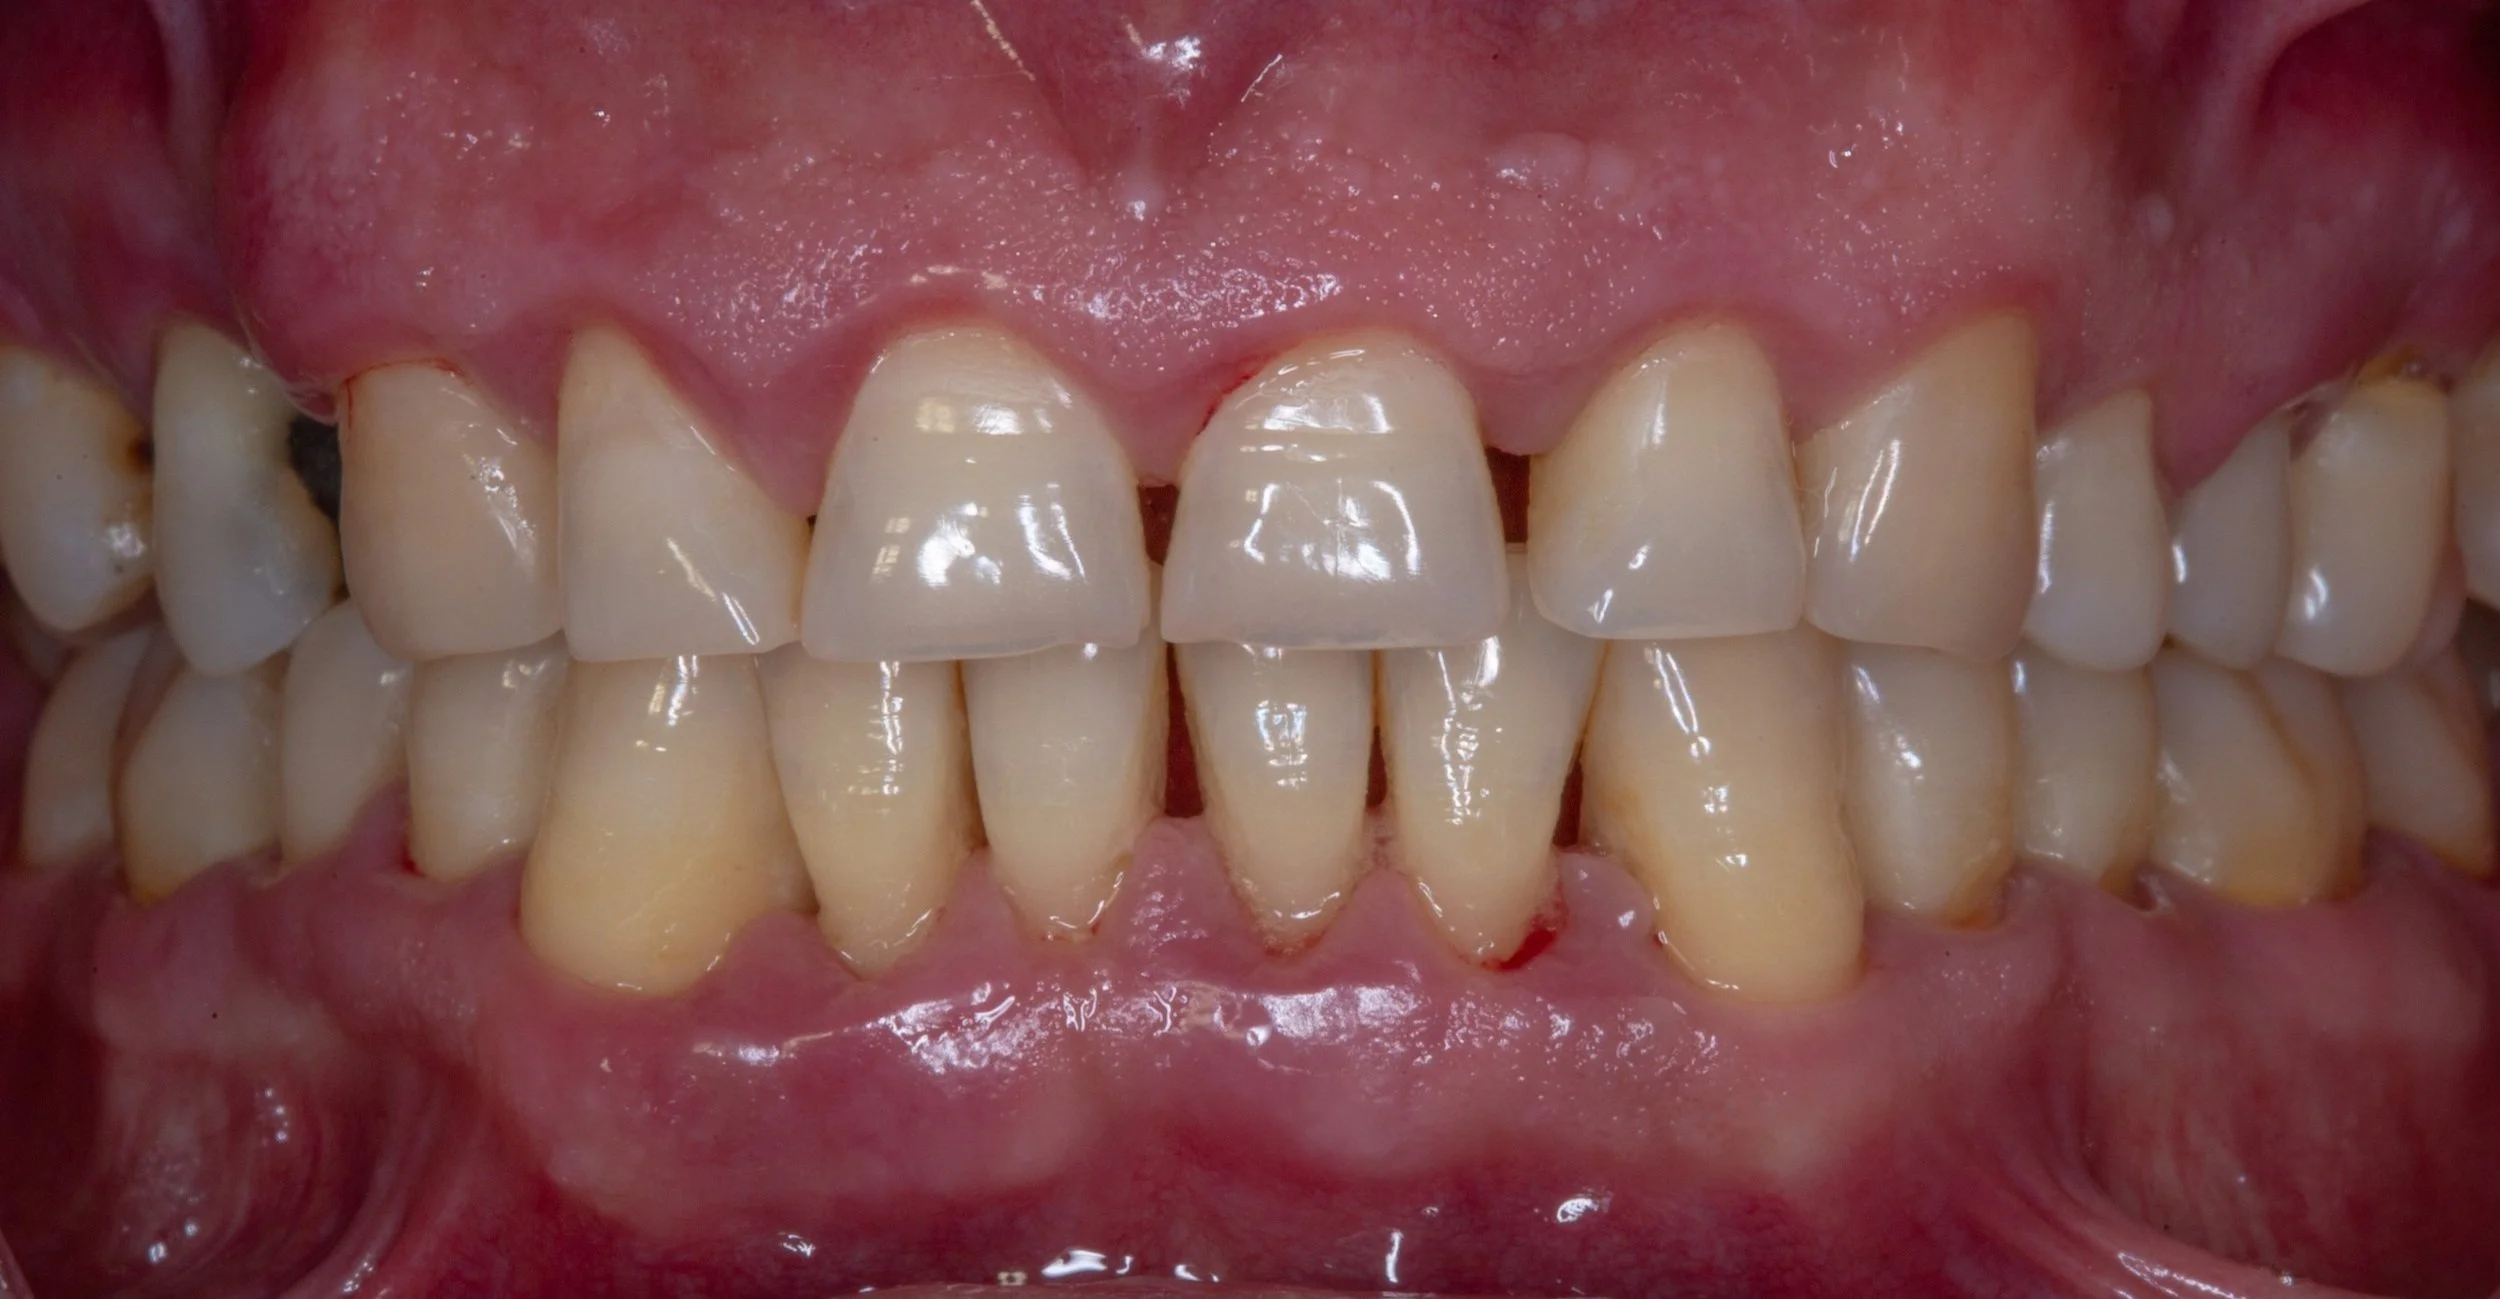

Sensitivity to cold, or bleeding after brushing your teeth may indicate gum recession. This occurs when your gums pull away from your tooth, exposing the root surface which may be uncomfortable or unsightly.